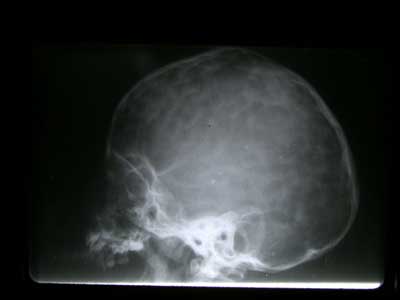

– Escafocefalia: Es el cierre de la sutura sagital. Es la deformidad más frecuente (50%). El cráneo adopta la forma de la quilla de un barco (de ahí su nombre), con un aumento del diámetro fronto-occipital (también se denomina dolicocefalia) y una disminución del diámetro biparietal (Fig.6)

Ya cada vez es más raro que diagnostiquemos una craneoestenosis en edades tardías. En estos casos podemos ver incluso huella digitiformes en las Rx de cráneo, señal de haber existido una hipertensión intracraneal (HIC) (Fig.10). Cuando el niño es mayor de 4-6 años, el problema se plantea sobre si la apertura de las suturas va a ser útil, en cuanto a permitirle un mejor desarrollo intelectual. En caso de duda, es muy útil monitorizar la presión intracraneal a lo largo de 24-48 horas. En caso de observar signos de HIC, se procedería a abrir las suturas, para dejar al cerebro crecer y evolucionar.